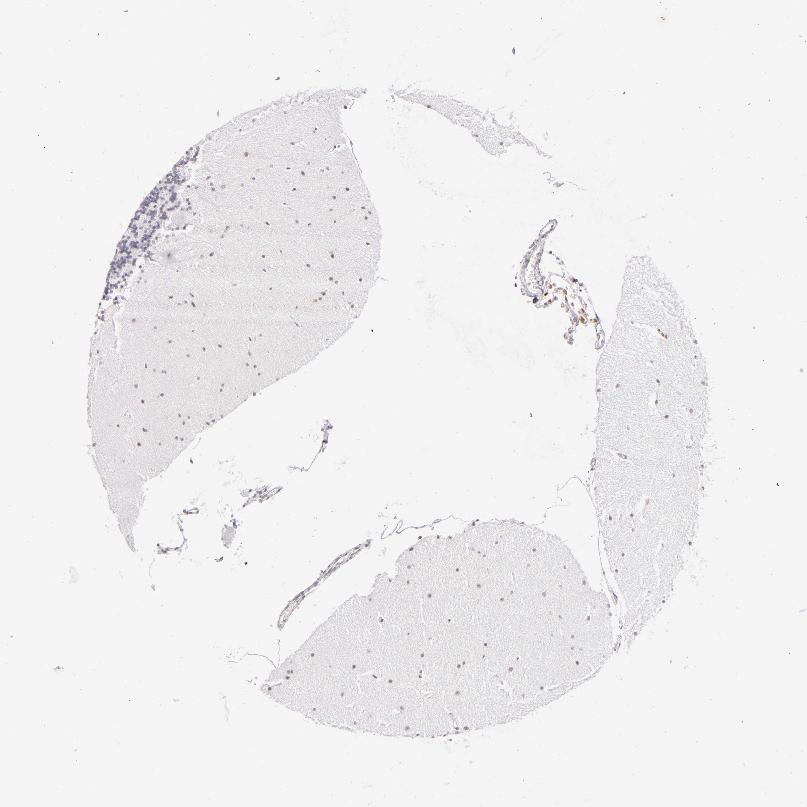

CEREBELLUM - Antibody stainingi

Antibody staining in the annotated cell types in the current human tissue is reported as not detected, low, medium, or high, based on conventional immunohistochemistry profiling in selected tissues. This score is based on the combination of the staining intensity and fraction of stained cells.

Each image is clickable and will lead to virtual microscopy that enables deeper exploration of all samples and also displays staining intensity scores, fraction scores and subcellular localization as well as patient and tissue information for each sample.

Antibody CAB002449

Purkinje cells Not detected

Cells in granular layer Low

Cells in molecular layer Not detected